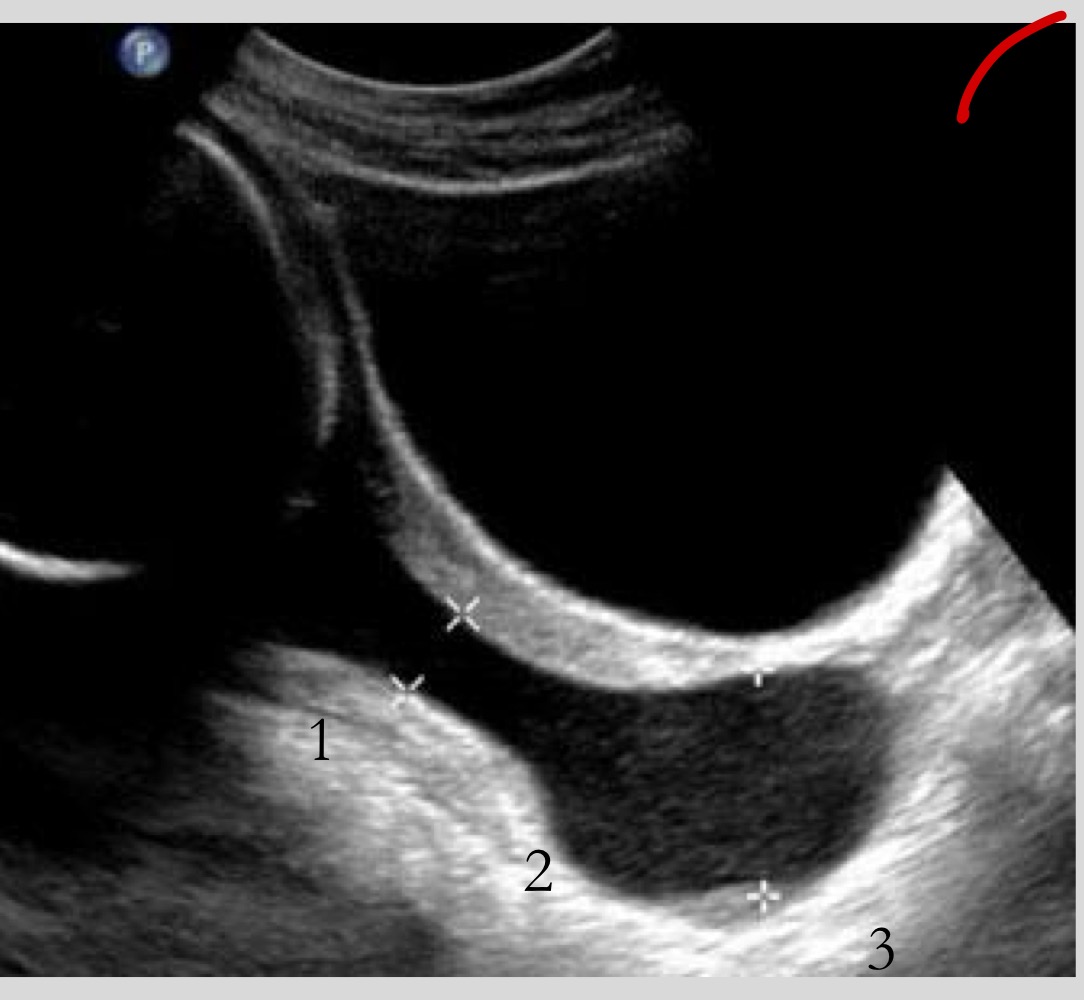

What is a false placenta previa

Apparent previa caused by lower uterine segment contraction

What should you do if a contraction mimics previa

Rescan in 10-20 minutes

What must be done before diagnosing placenta previa

Post-void scan or transvaginal ultrasound